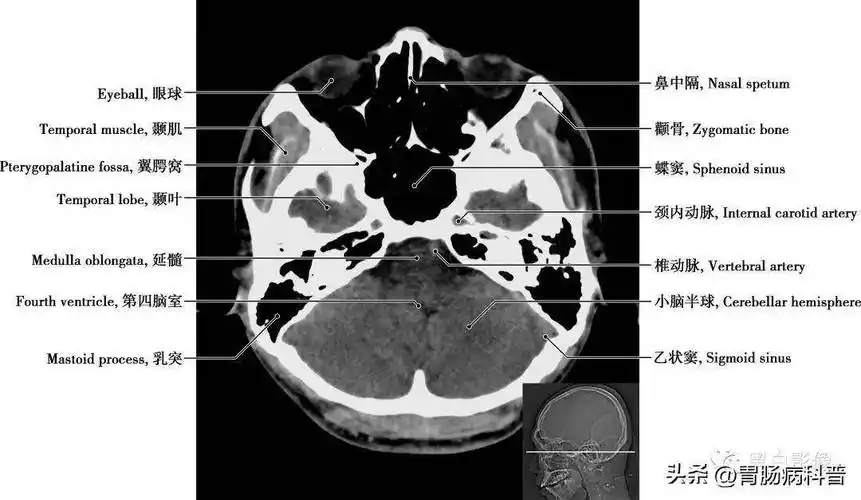

详细标注版——颅脑ct正常解剖图谱_中央_小脑_纤维